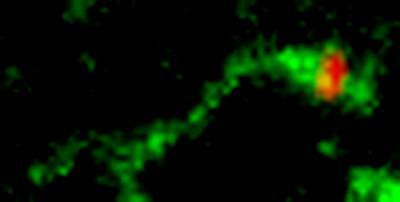

In early endosomes, Shiga toxin (green) is sorted into membrane tubules, which pinch off and move to the Golgi apparatus. The membrane left behind, marked by epidermal growth factor (red), eventually fuses with lysosomes and its contents are destroyed. Sorting into the Golgi-destined membrane tubules depends on Shiga toxin binding to GPP130. Manganese protects cells by down-regulating GPP130. Without GPP130 to bind, Shiga toxin does not enter the endosomal membrane tubules and, as a consequence, it is degraded in lysosomes.

(Photo Credit: Carnegie Mellon University)